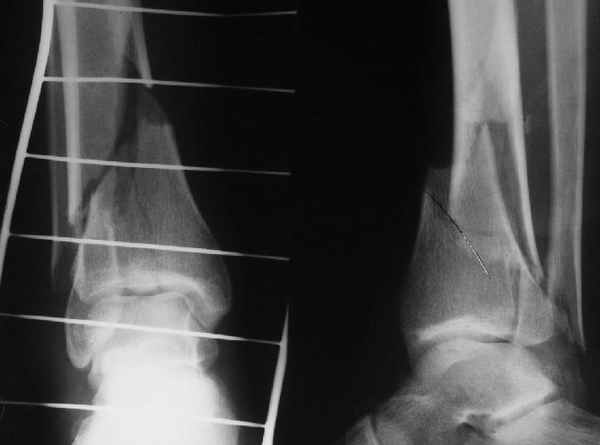

АЧ>Какие тут аргументы в пользу выбора пластины, а не интрамедуллярного гвоздя?

Классически показанием для locked nail яв-ся зоны BC CD, до появления LCP показания к locked nail несколько расширялись в зоны AB и DE

Аргументы: перелом достаточно низкий, трудно будет ввести 3-и блок. винта, а учитывая характер перелома на 2-х дистальных винтах я бы не рекомендовал немедленную полную нагрузку.

С Уважением А.Миронов

Кликните для загрузки файла DSC00841.JPG

42KB (43152 bytes)

АМ> Аргументы: перелом достаточно низкий, трудно будет ввести 3-и блок.

АМ> винта, а учитывая характер перелома на 2-х дистальных винтах я бы не

АМ> рекомендовал немедленную полную нагрузку.

Положим, и с 2 винтами она к 2 месяцам была бы тут вполне реальна. Кроме того, есть возможность ввести винты мимо гвоздя (Poller), и таки разрешить раннюю полную нагрузку (что еще зависит от массы тела пациента и диаметра винтов). А уж если сопоставить стоимость отечественного гвоздика и пластины Synthes... Если бы на порядок более дорогая железка давала на тот же порядок лучший результат... ;-)